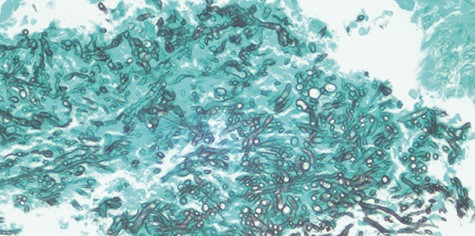

Gomori’s methenamine silver (GMS) stain of Candida species evidenced by its septate hyphae with characteristic dichotomous branching at an angle of approximately 450.